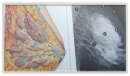

Breast Cancer Seminar

DR M.A MOHAMMADI RADIOLOGIST

Amirkabir Medical Imaging Centre